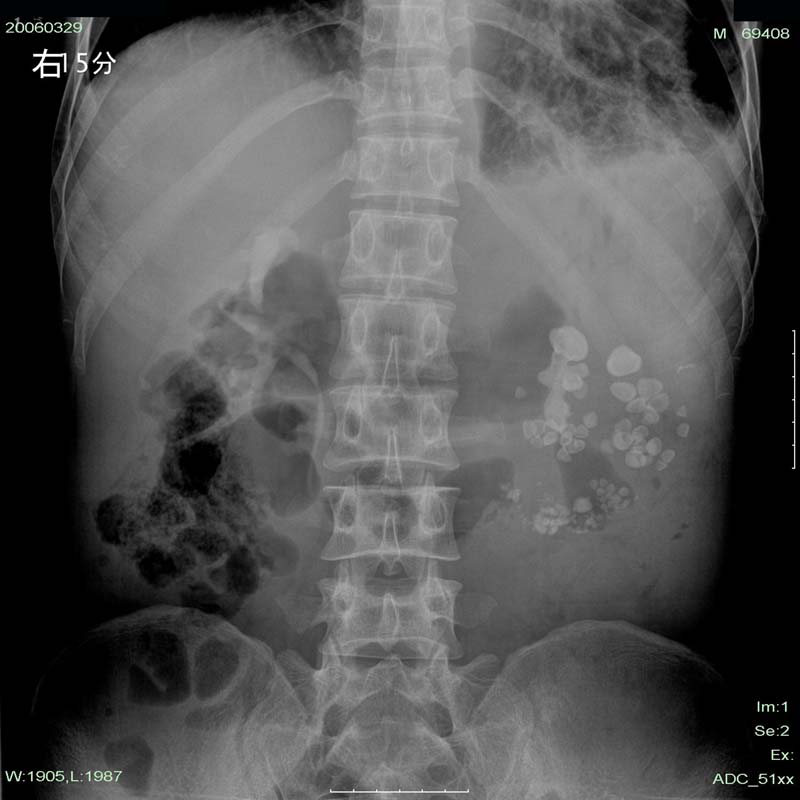

下午做的检查,第二天早上透视,左肾区仍未见造影剂显影。

这个是左肾多发性结石伴重度积水。其与肾自截不同的是:肾自截呈全肾钙化,肾脏缩小.本例肾内密度增高影呈颗粒状,肾影增大.故不支持肾自截

本例造影过程中结石位置,大小等都未有明显改变。左肾体积明显增大,与肾自截相反。且无钙化。故支持向医生的观点。

从这份片上我们可以看到左肺心影响后肺纹理增强紊乱,可见蜂窝状改变,且左侧肋膈角变顿,胸膜粘连。可能肺有慢性肺病(结核?)。从腹部片看,左肾区多发结石影可以肯定,但其下部可见一些斑条状致密影,不能排除是钙化。左肾轮廓并未显示清楚且位置较右肾还低。所以本人认为左肾多发结石并重度积水要考虑,尚需考虑肾自截可能,建议加拍胸片明确胸部情况并行双肾ct扫描。

左肾上极见“鹿角”样结石并中下极多发性结石。左肾重度积水,在该片只是推理而已,左肾没有看到肾盂、肾盏显影。从结石分布看,可以肯定不是肾自截钙化。